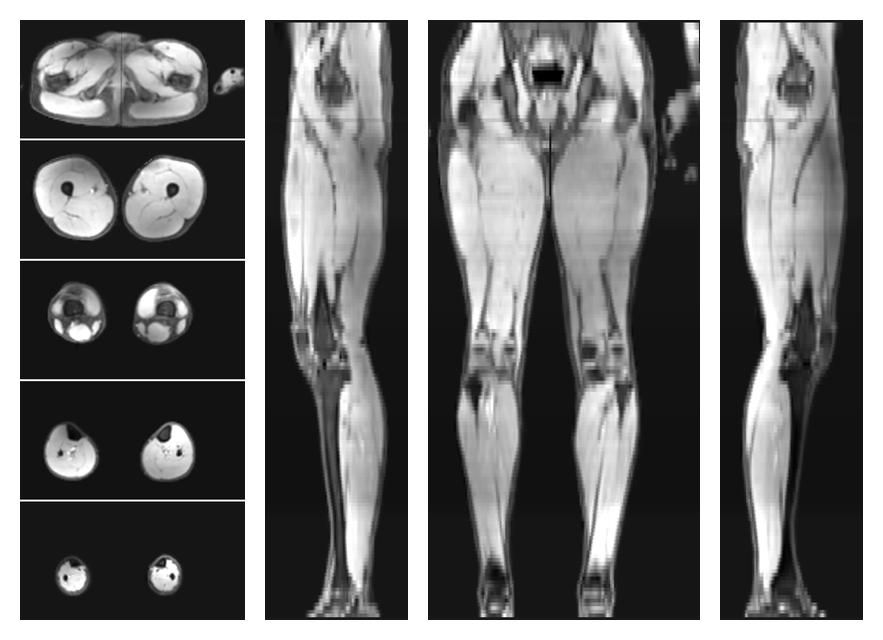

• Water only signal

The water part of the acquired multi-echo spin echo data.